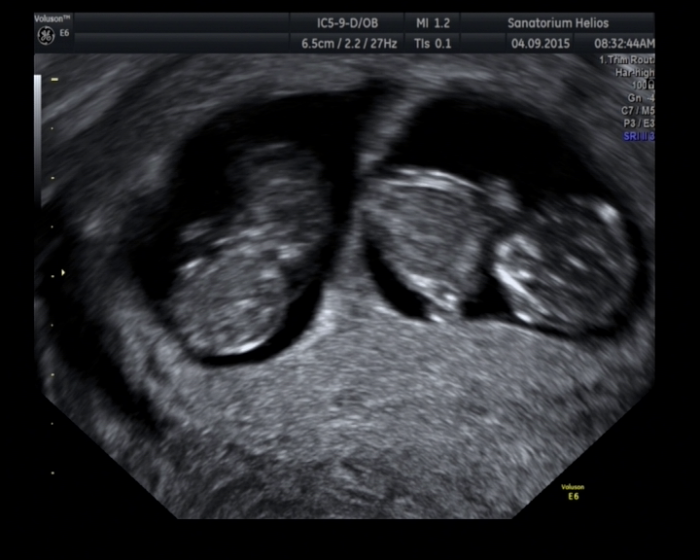

Ahoj holky, jen hlásím ve zkratce, že po včerejším UTZ je zatím vše OK. Tak nějak odpovídáme, a další týden je screening. Pak podám hlášení, zda je vše OK. Docela se bojím.... přikládám foto.

Luci, jeeeee, to jsou uz uplne hotova mimnka :) jsou nadherny!!!! Victory, drzim palce, at vajicko oplodnilo a prkne uhnizdilo. To cekani je na tom nejhorsi, ale zase nadeje je to, co nas drzi mad vodou!!

LUCI - to je taková nádhera, opravdu mě to dojalo, jsem z toho naměkko... Chodíš do práce, nebo jsi doma?Kéž bys měla pravdu a spermucha tam to vajucho oplodnila, ale když člověk všude čte, co je k tomu všechno potřeba, dojde mu, že je to prostě takový zázrak, že se to obyčejným lidem nestává...Na tribulus mrknu. Manžel má spermi OK, ale přeci jen raději bere selzink...